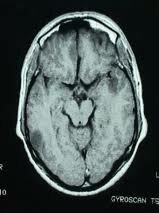

Hipócrates

Describió el cerebro como el intérprete de la consciencia y el órgano más importante del cuerpo en sus esfuerzos por explicar por qué la gente se comportaba como lo hacía.

• Franz Joseph Gall (1758-1828) Frenología

Franz Joseph Gall (1758-1828) Frenología

Las distintas “facultades” psicológicas se localizaban en áreas específicas del cerebro, creía que las protuberancias y hendiduras en la superficie del cráneo eran reflejos precisos de las partes del cerebro subyacentes.